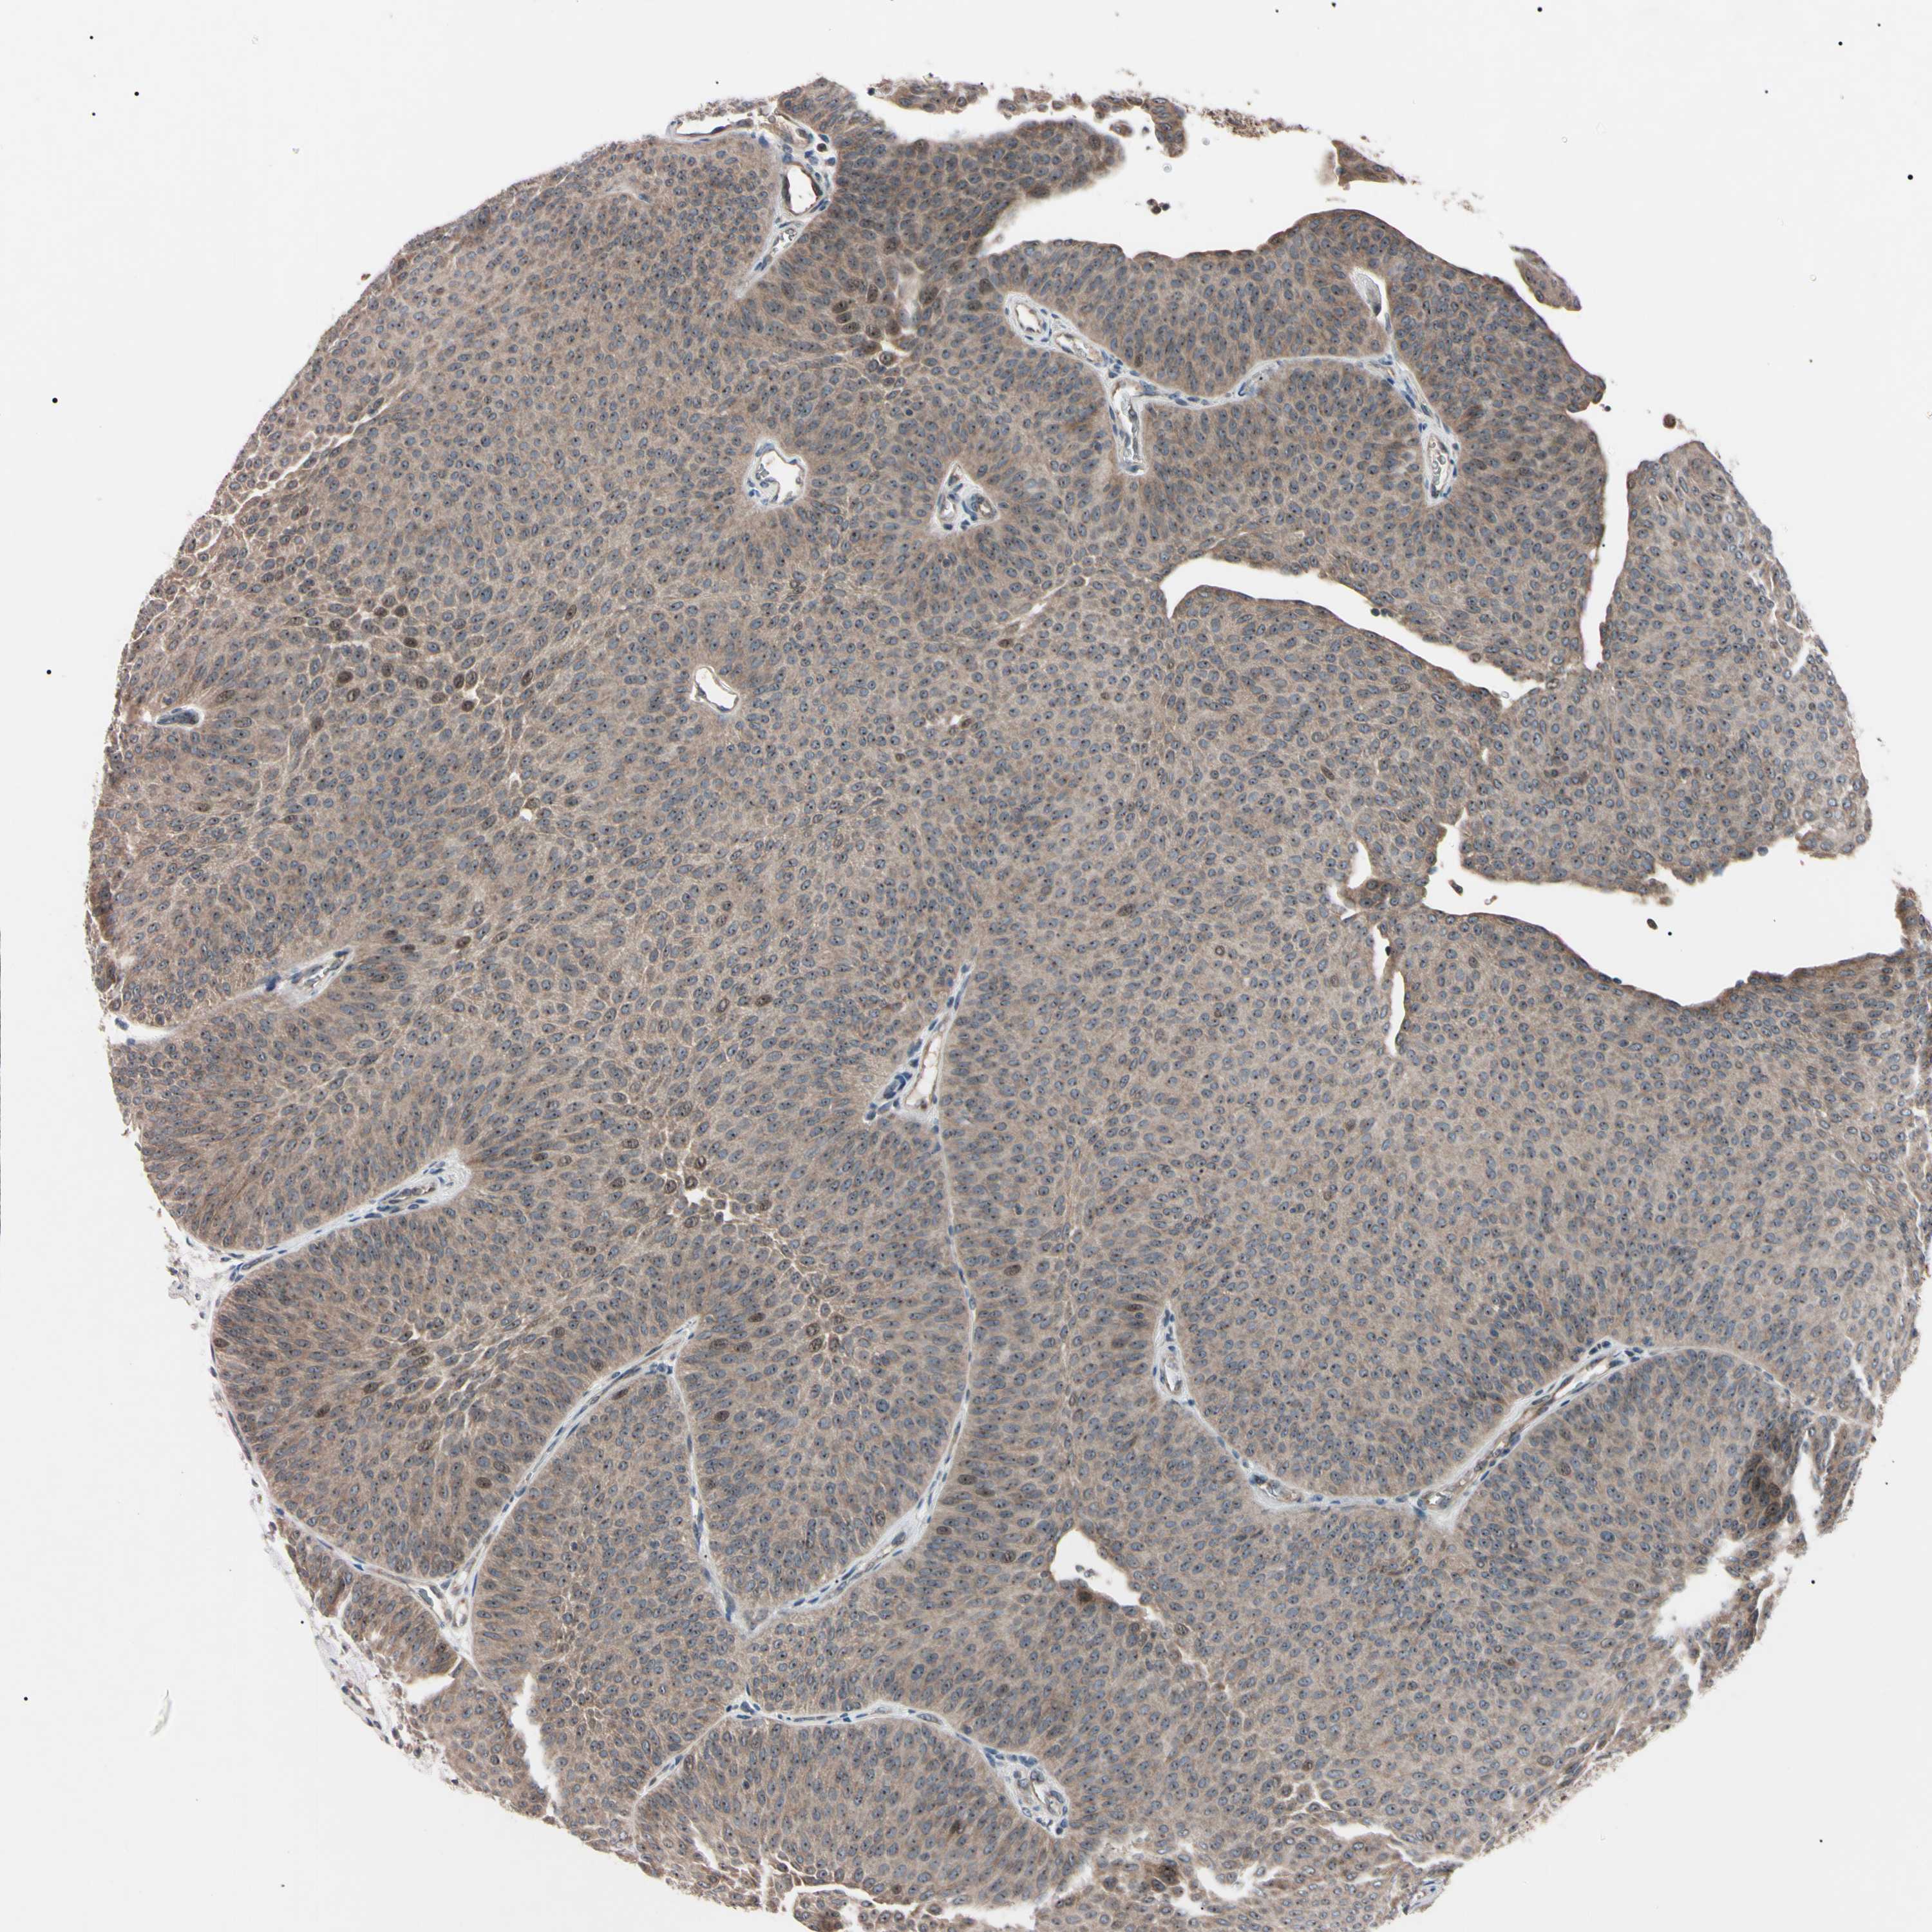

UROTHELIAL CANCER - Protein expressioni

A mouse-over function shows sample information and annotation data. Click on an image to view it in a full screen mode. Samples can be filtered based on level of antibody staining by selecting one or several of the following categories: high, medium, low and not detected. The assay and annotation is described here.

Note that samples used for immunohistochemistry by the Human Protein Atlas do not correspond to samples in the TCGA dataset.

Antibody stainingi

Antibody staining in the annotated cell types in the current human tissue is reported as not detected, low, medium, or high, based on conventional immunohistochemistry profiling in selected tissues. This score is based on the combination of the staining intensity and fraction of stained cells.

Each image is clickable and will lead to virtual microscopy that enables deeper exploration of all samples and also displays staining intensity scores, fraction scores and subcellular localization as well as patient and tissue information for each sample.

Antibody HPA008052

Antibody CAB010277

Staining

High

Medium

Low

Not detected

Intensity

Strong

Moderate

Weak

Negative

Quantity

>75%

75%-25%

<25%

None

Location

Nuclear

Cytoplasmic/membranous

Cytoplasmic/membranous,nuclear

Urothelial carcinoma, Low grade

Urothelial carcinoma, High grade